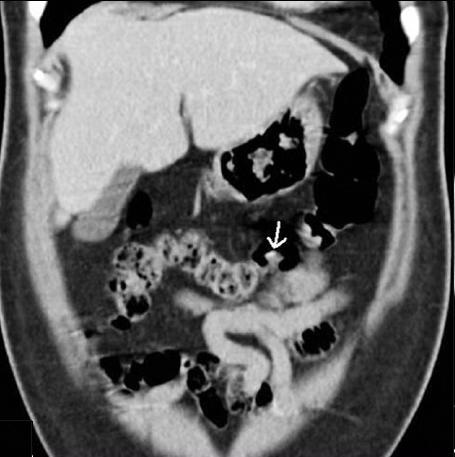

Image d'une polyp du colon

transverse a aspect polypoide hyper-dense avec une

large pedicule ( fleche blanche ) Polyp du colon

transverse en image radiologique TDM coupe axiale |

Aspect polypoide d'une polyp

du colon en coupe axiale du TDM . Image

radiolologique en ce cas est une polyp a petite

pedicule en forme du champignon ( fleche rouge ) |